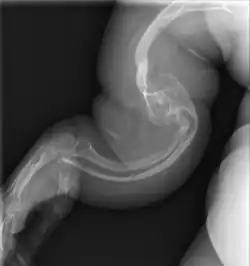

Left forearm

Spine, chest, and pelvis

Right forearm

Right femur

Four X-rays of a 24-year-old American man (Fredrick Brennan), who had had more than one hundred bone fractures in his lifetime, and received a childhood clinical diagnosis of type IV–B OI. Genetic diagnosis in 2018 identified a previously uncatalogued pathogenic variant in the gene which encodes proα2(I) chains of type I procollagen, COL1A2, at exon 19, substitution c.974G>A. Due to childhood neglect and poverty, Brennan never received surgery to implant intramedullary rods. Malunions are evident as the humerus and femur were broken in adolescence, but orthopedic care did not follow. Severe scoliosis, as well as kyphosis, are also evident. The unavoidably low contrast in the film is due to a combination of Brennan's obesity and low bone mineral density (BMD). His BMD Z-score was -4.1 according to results of a dual-energy X-ray absorptiometry (DXA) scan also done in 2018.